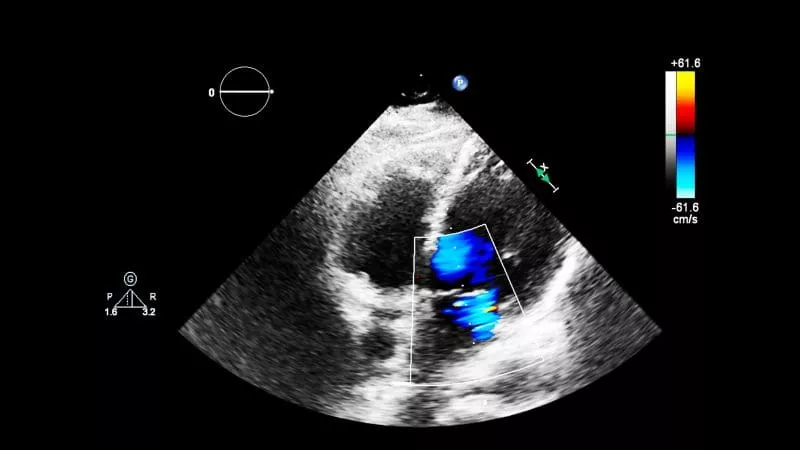

Ultrasound uses high-frequency sound waves—never radiation—to create live, real-time 3D images of your body’s internal structures. When these images are captured over time to show motion, it’s known as 4D ultrasound. This safe, painless exam helps your doctor evaluate organs, tissues, and blood flow and is commonly used for pregnancy, vascular, abdominal, and soft-tissue evaluations. A technologist gently moves a handheld transducer across the skin with warm gel to capture the images, and most exams take just 15–30 minutes.

At SimonMed, we pair this trusted technology with advanced innovations, including pioneering work in automated 3D and 4D breast ultrasound (ABVS/ABUS) for high-resolution cancer evaluation, enhanced 3D thyroid imaging for precise nodule assessment, and elastography to measure liver stiffness and detect early tissue changes. After your scan, a radiologist reviews the images and sends a clear report to your provider to guide next steps.